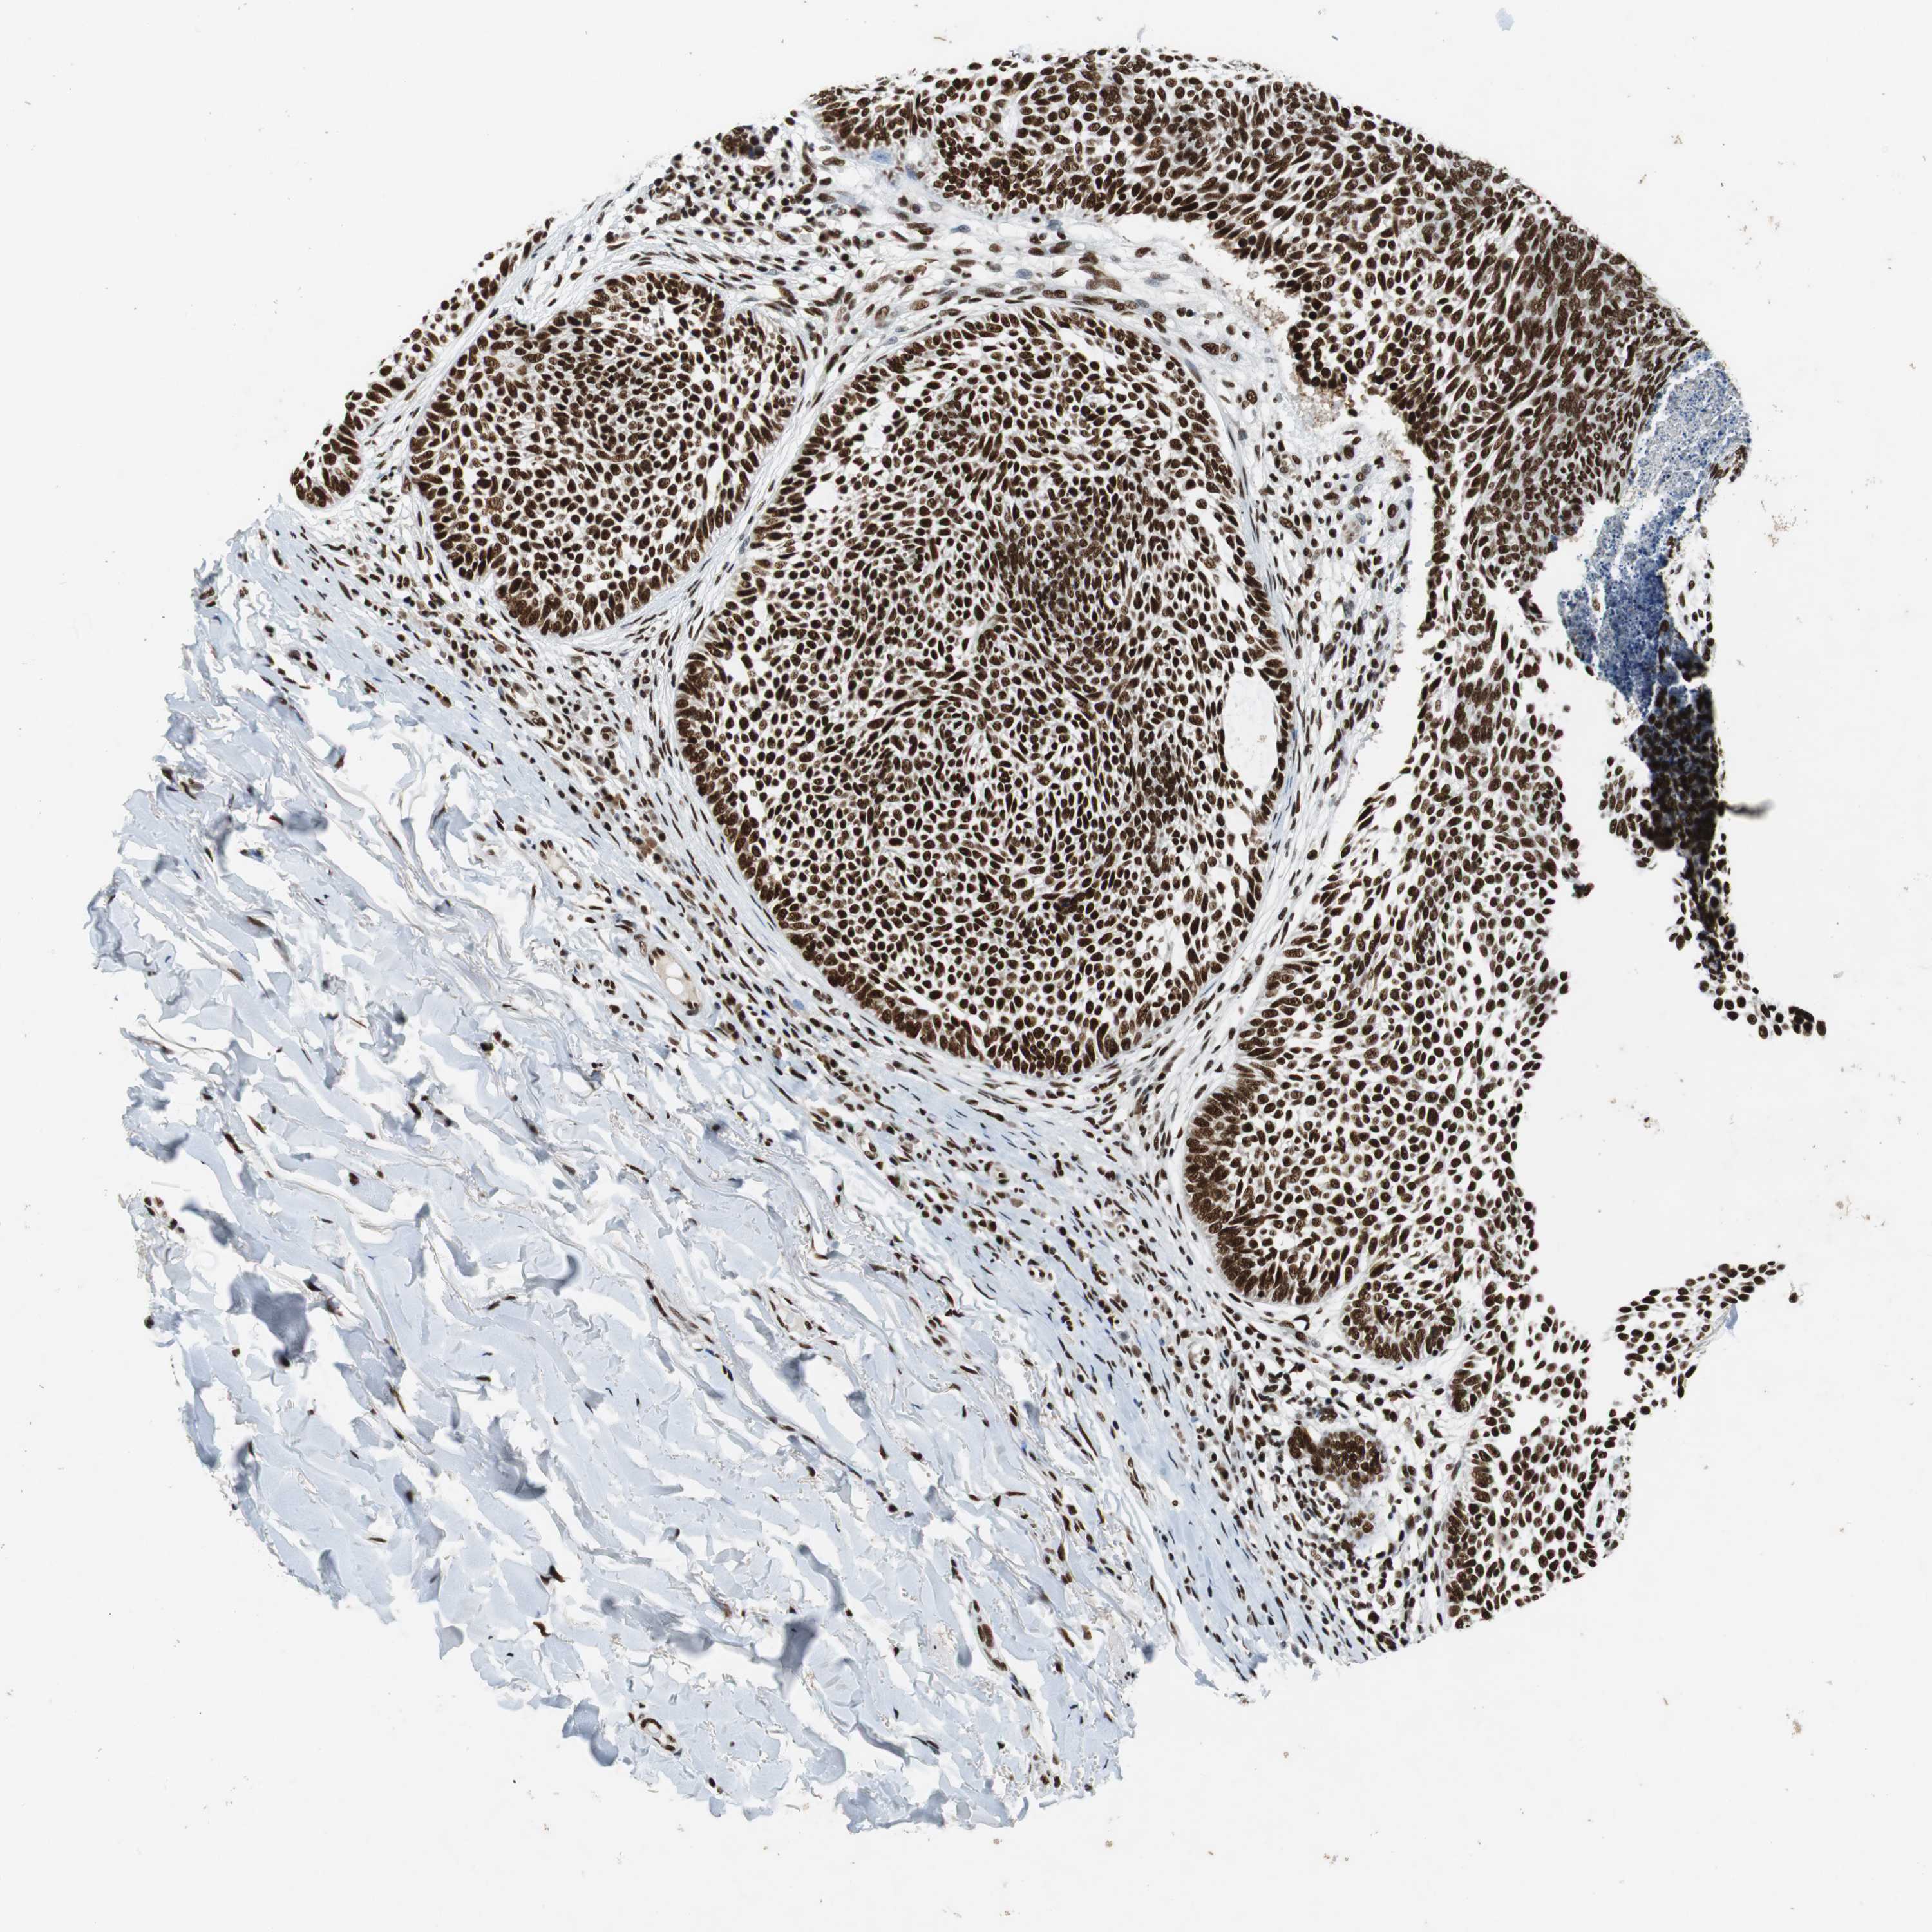

SKIN CANCER - Protein expressioni

A mouse-over function shows sample information and annotation data. Click on an image to view it in a full screen mode. Samples can be filtered based on level of antibody staining by selecting one or several of the following categories: high, medium, low and not detected. The assay and annotation is described here.

Antibody staining in the annotated cell types in the current human tissue is reported as not detected, low, medium, or high, based on conventional immunohistochemistry profiling in selected tissues. This score is based on the combination of the staining intensity and fraction of stained cells.

Each image is clickable and will lead to virtual microscopy that enables deeper exploration of all samples and also displays staining intensity scores, fraction scores and subcellular localization as well as patient and tissue information for each sample.

Antibody HPA035174

Antibody CAB005167

Staining

High

Medium

Low

Not detected

Intensity

Strong

Moderate

Weak

Negative

Quantity

>75%

75%-25%

<25%

None

Location

Nuclear

Cytoplasmic/membranous

Cytoplasmic/membranous,nuclear

Squamous cell carcinoma, NOS